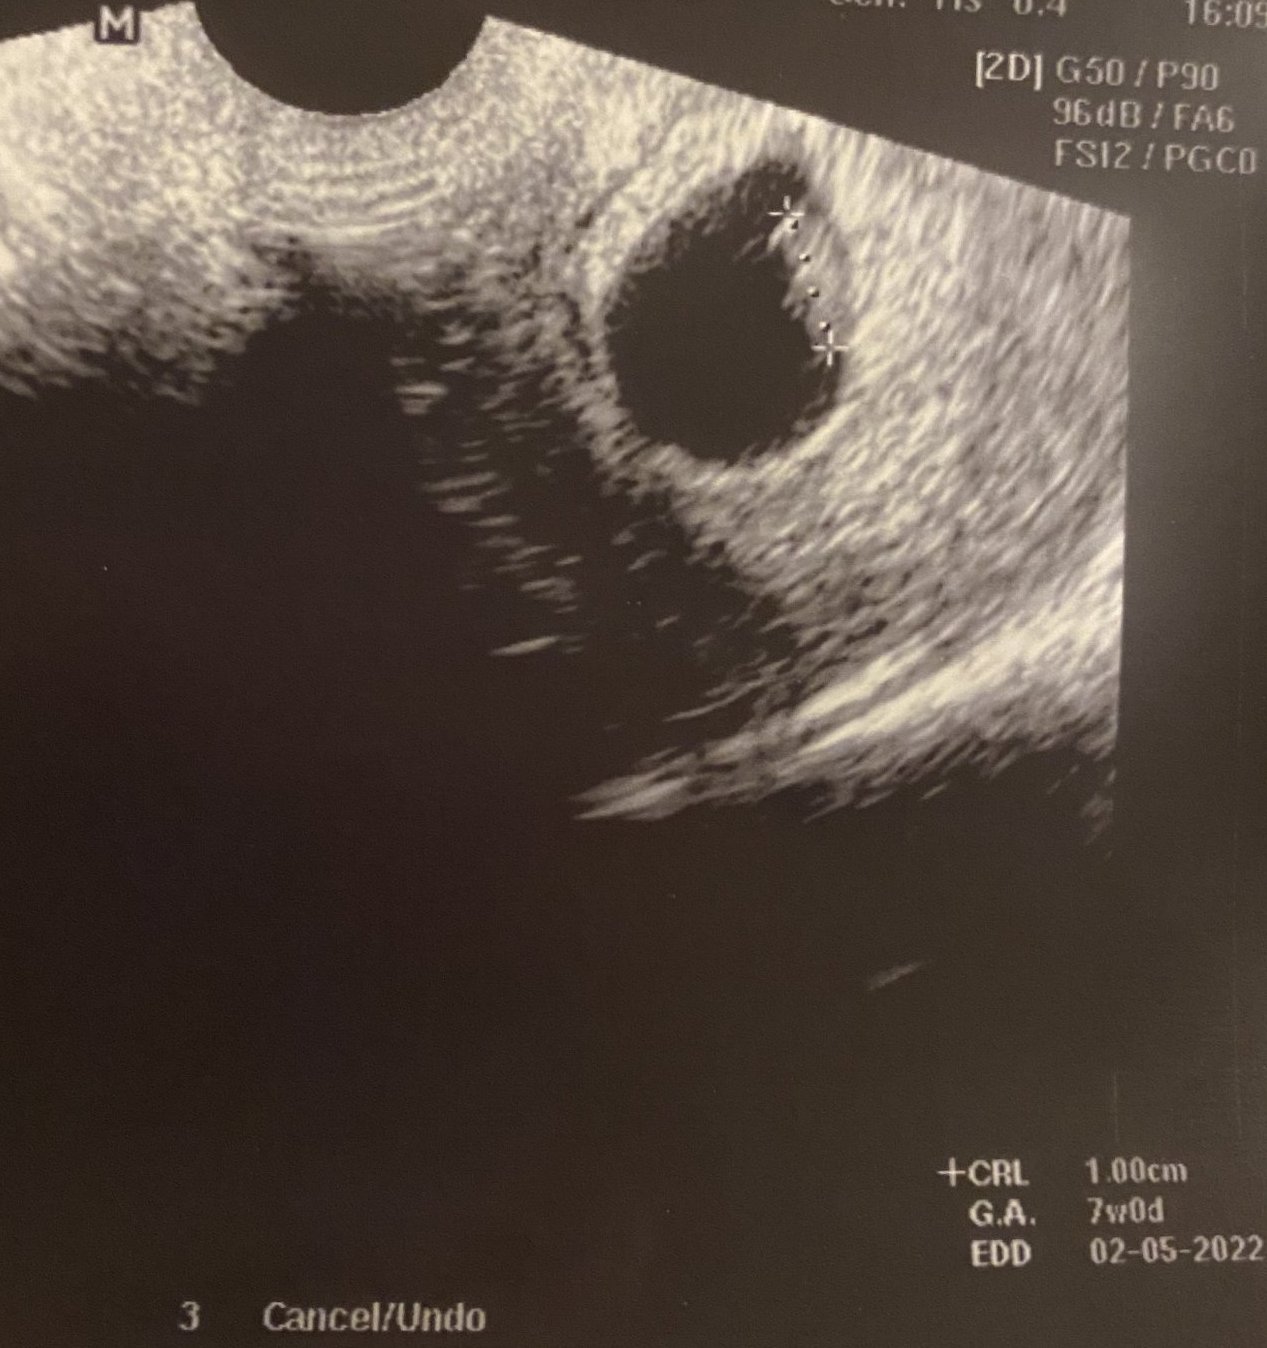

Майките споделят различни симптоми на бременност, като болезнени и подути гърди, гадене, стомашни болки, умора, замаяност, болки в кръста, наддаване на тегло в областта на корема , сутрешно гадене , повишена чувствителност на гърдите и повишена сънливост. Важно е да се отбележи обаче, че симптомите на бременността могат да варират значително между отделните жени. Някои от споделените симптоми включват гадене, често уриниране през нощта, умора, чувствителност и напрежение в гърдите, киселини в стомаха, главоболие и промени в обонянието. Важно е да се отбележи обаче, че симптомите на бременността могат да варират значително от жена до жена. Хората във форума споделят различни симптоми на бременност като гадене, повръщане, киселини, болезнени гърди, главоболие, умора, запек , повишен апетит , увеличен обем на корема , кафяво течение , умора и чувство на напрежение в корема. Жените в бременност често изпитват различни симптоми като главоболие, гадене, умора и промени в настроението поради хормони. Те могат също да изпитат физически дискомфорт като подуване, коремна болка и различни зацапвания. Тези усещания понякога могат да бъдат стресиращи и тревожни относно здравето на плода. Въпреки това, много жени намират успокоение от редовните медицински прегледи и уверенията, че бебето е добре.